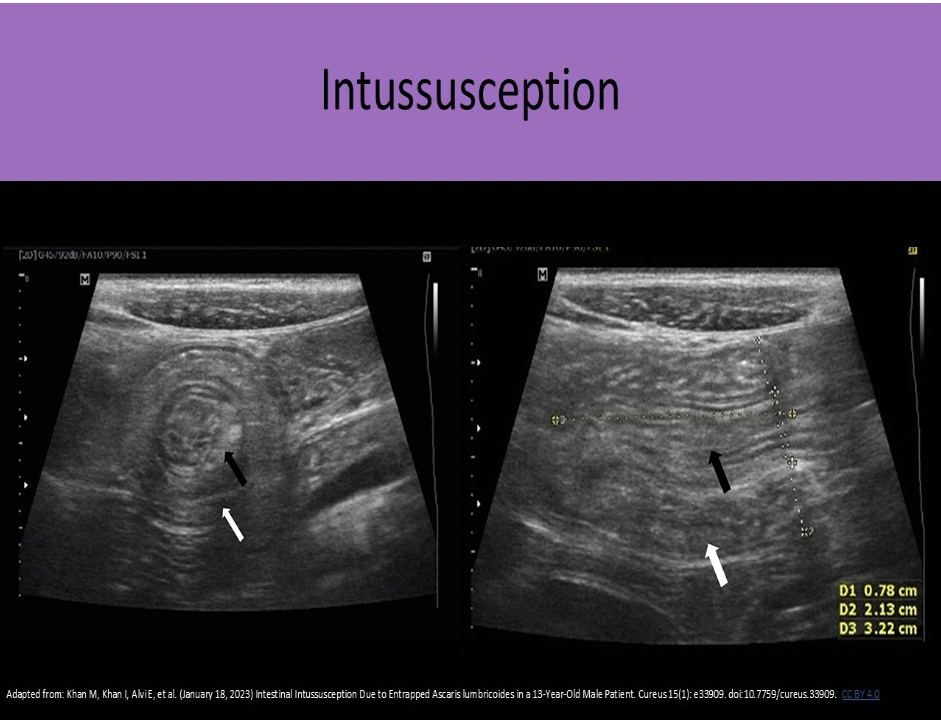

A 2yr old presents with a swollen abdomen and pain for 3 days. The doctor suspects an intussusception is present. How will this appear on the exam?

A. fluid filled colon with multiple intramural masses

B. prominent focal area of concentric rings of bowel

C. fluid filled colon with inflamed walls

D. thickened pylorus muscle

An intussusception refers to a segment of bowel that involutes into itself. You will see a focal area of concentric rings of bowel that do not persitalse or change shape.

The term used to describe the involution of the small bowel upon itself is:

A. intussusception

B. colitis

C. Crohn syndrome

D. irritable bowel syndrome